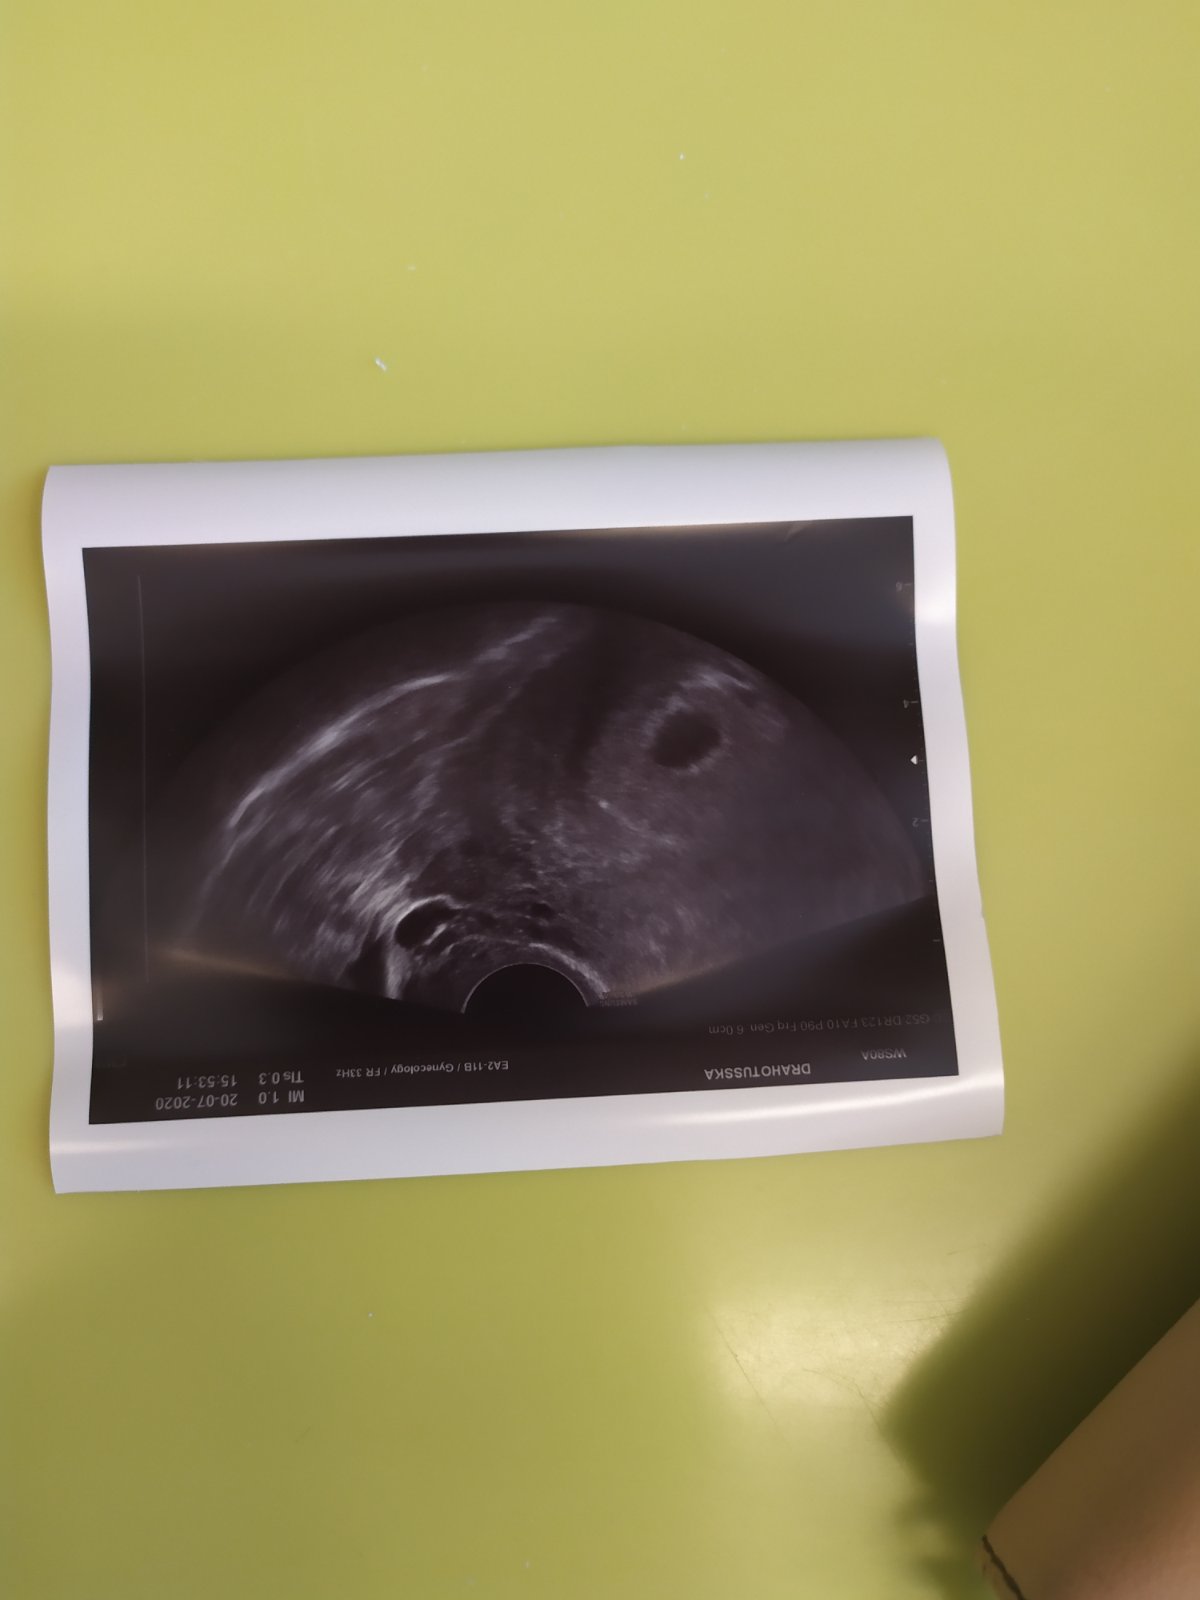

Ahoj holky 😊, zdravím po 1.kontrole, kde mi bylo potvrzeno těhotenství v děloze, vše odpovídá týdnu těhotenství.

Přeji vám všem, ať dopadnou 1.kontroly na jedničku ❤️. Mě čeká další za 14. dní 😊